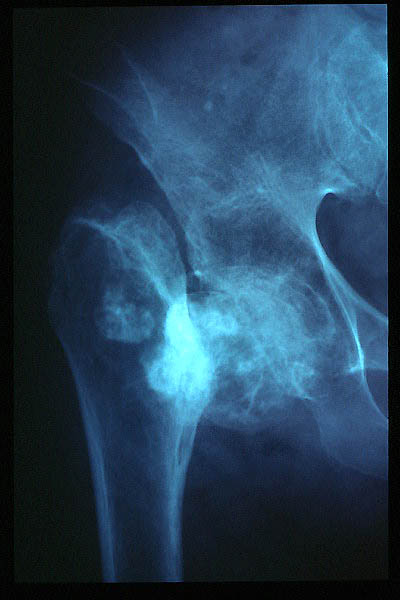

Artrosis avanzada de cadera. Anquilosis.

Artrosis anquilosante de cadera.

Atrosis avanzada de cadera.